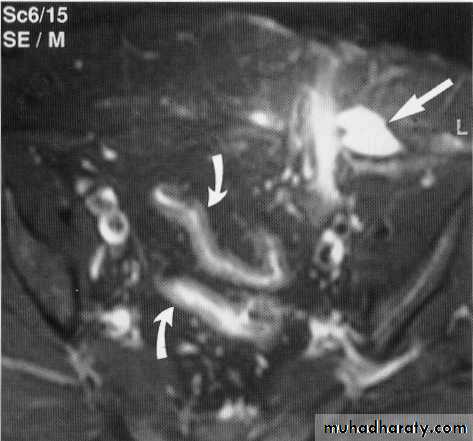

Colono-vesical fistula